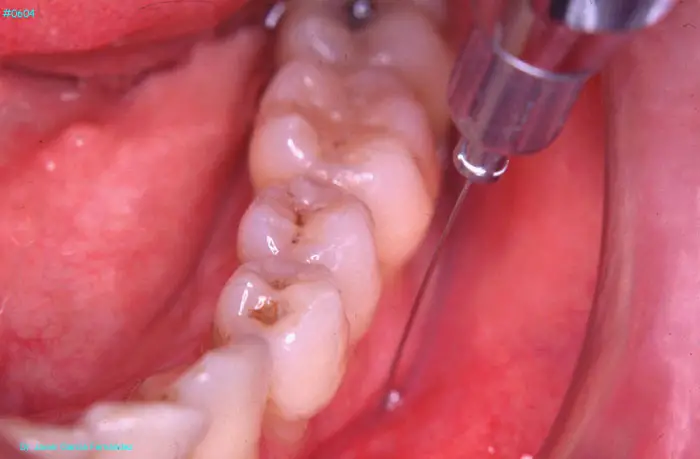

Atlas of Surgical Techniques in Periodontics. Chapter II. Atlas de Técnicas Quirúrgicas en Periodoncia